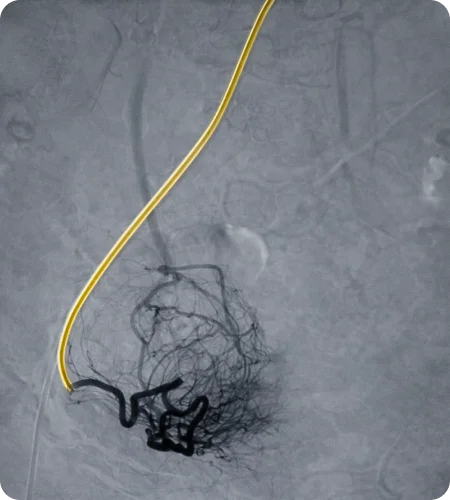

Varicocele

Embolisation

Varicocele embolisation is a non-surgical treatment for enlarged veins in the scrotum that can cause discomfort or fertility issues. Using image guidance, a small catheter is used to block the abnormal veins, restoring normal blood flow and relieving symptoms.